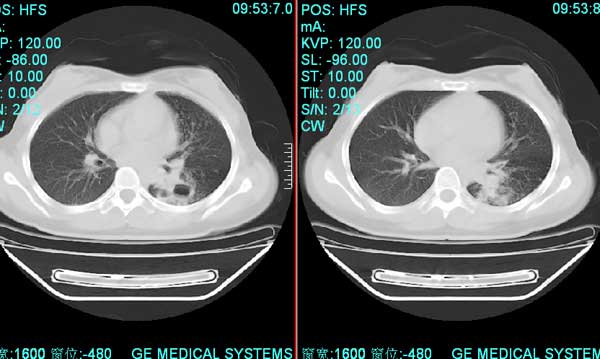

以下是引用pujunzhi在2008-7-1 20:03:00的发言:[br]支持楼主意见!两肺继发性肺结核伴多发空洞形成。